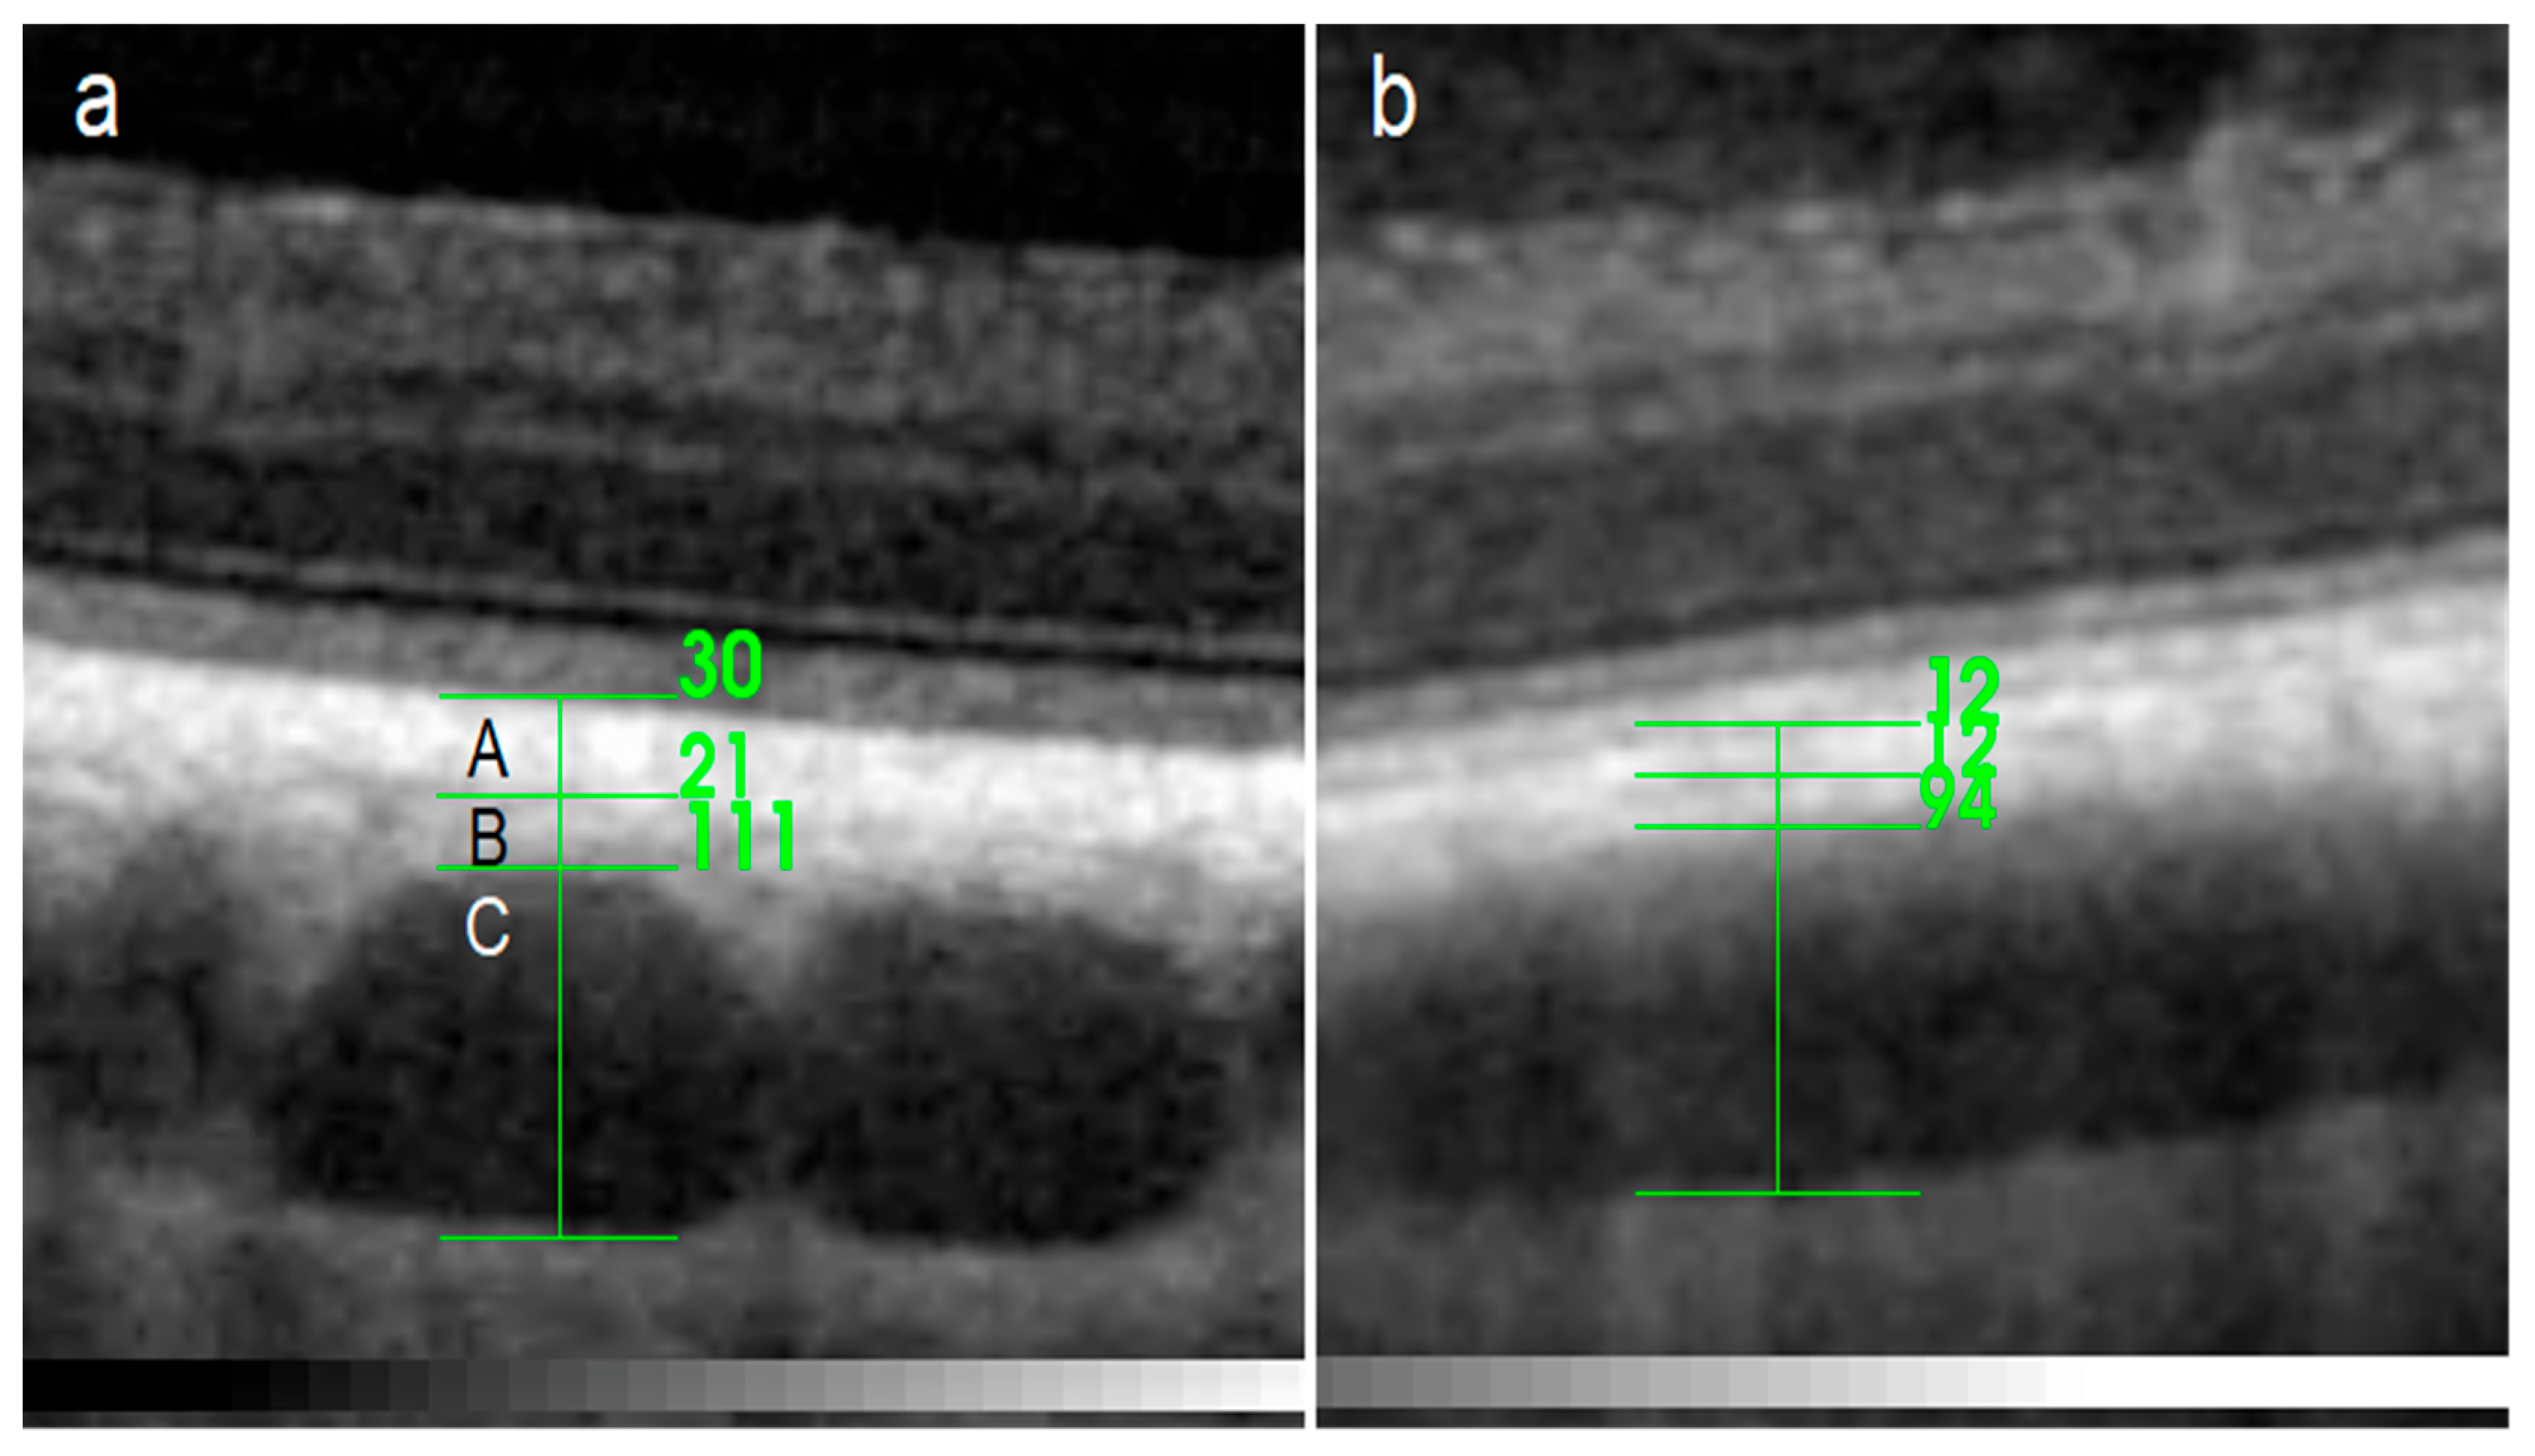

3. Results